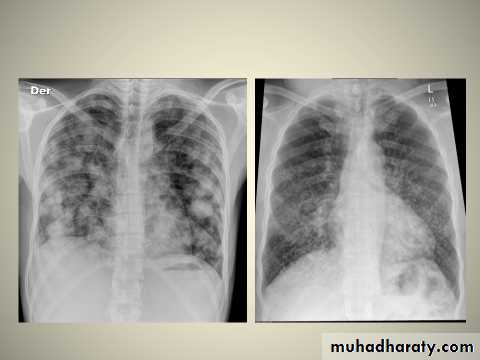

Bronchopneumonia

chest X-ray

Bronchopneumonia (also sometimes known as lobular pneumonia ) is a radiological pattern associated with suppurative peribronchiolar inflammation and subsequent patchy consolidation of one or more secondary lobules of a lung in response to a bacterial pneumonia.